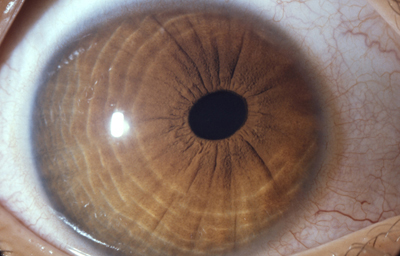

Síndrome Endotelio-Irido-corneal, = ICE (Iridocorneal Endothelial Syndrome)

Grupo de alteraciones caracterizado por anomalias proliferativas del endotelio corneal, anormalidades en el Iris y del ángulo de la cámara anterior. Clínicamente se observa edema de la córnea, atrofia del Iris, anomalías pupilares y glaucoma.

Abarca tres variantes 1) El Sindrome de Chandler.- 2) La Atrofia Esencial del Iris.-3) El Síndrome de Cogan-Reese ( Nevus del Iris)

Patológicamente aparece como una enfermedad adquirida en la que las células endoteliales adquieren características de células epitelioides, con habilidad migratoria, tonofibrillas y desmosomas. Se considera que el aspecto del “Endotelio-martillado de color plata” es un signo diagnóstico.

Tipicamente es unilateral, progresivo, con predominancia femenina, se manifiesta al inicio de la vida adulta (20-50 años) y no se asocia a malformaciones sistémicas.

Etiología desconocida; se plantea posibilidad de relación con el virus del Herpes.

El Sindrome de Chandler. Se llama así, cuando los cambios patológicos están limitados a la superficie interna de la córnea con alteración de la bomba endotelial, lo que produce edema de córnea. Si el endotelio anómalo invade el ángulo, se desarrolla glaucoma.

Sindrome de Chandler

Archivo fotográfico Dr. Francisco Barraquer

Sindrome de Chandler

Archivo fotográfico Dr. Francisco Barraquer